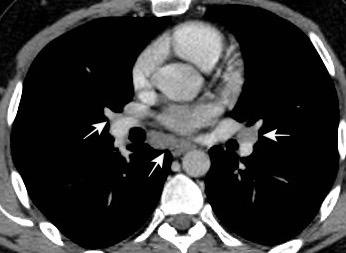

Triada de Garland

Ganglios paratraqueales derechos e hiliares bilaterales

95% de pacientes tienen ganglios hiliares bilaterales aislados o con afectación mediastínica (espec. paratraqueal derecho).

Criado E et al. Pulmonary sarcoidosis: typical and atypical manifestations at high-resolution CT with pathologic correlation. Radiographics. 2010